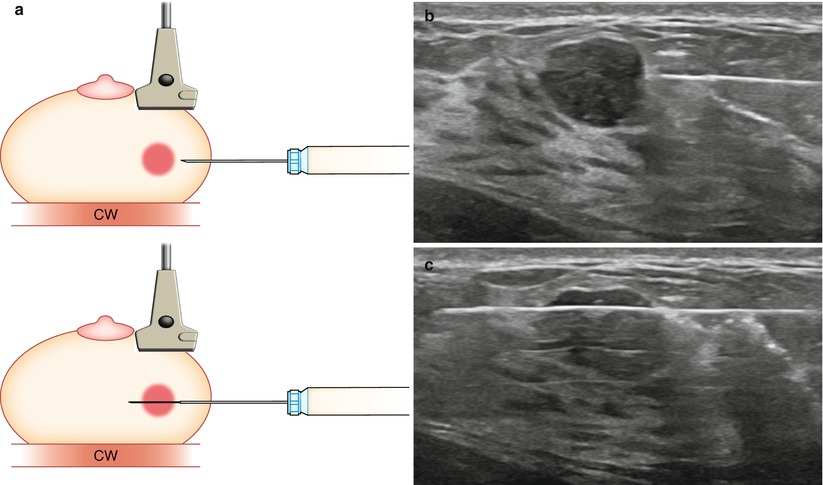

6. Core Needle Biopsy

A core needle biopsy removes a small tissue sample from the breast lump using a larger needle, often under ultrasound guidance.

• Provides more accurate diagnosis than FNAC

• Allows for hormone receptor and HER2 testing in cancer cases

• Essential before planning surgery or other treatments

As a surgical oncologist, I rely on the biopsy report to tailor the treatment precisely.